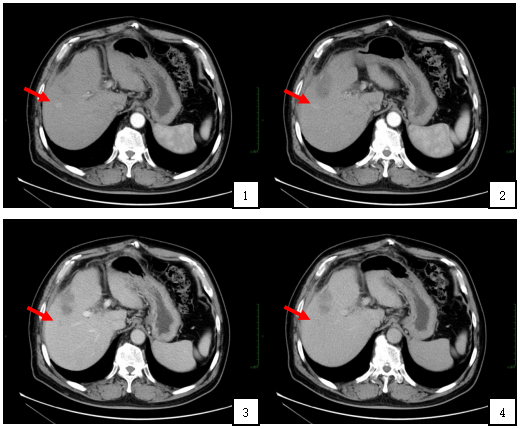

上腹部增强CT(门诊2019-3-20)结果回报:肝右叶强化结节,结合病史,考虑新发病灶;肝内多发局灶灌注异常,建议3-6个月复查;肝内囊肿,双肾囊肿;胆囊切除术后改变。

附图2:腹部增强CT显示:动脉期(图1,2)肝右叶可见高密度强化结节,直径约1.2cm,位置如箭头所示;静脉期和延迟期(图3,4)肝右叶结节呈低密度改变,位置如箭头所示。